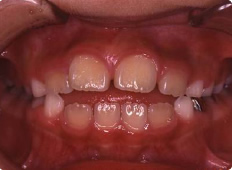

8歳女子

咬み合わせが反対である事が気になり来院されました。

口腔内に装置(リンガルアーチ)を装着し、フェイシャルマスクで上あごを前方へ牽引します。

【治療期間】

装置装着期間1年。

その後成長経過観察を行いました。